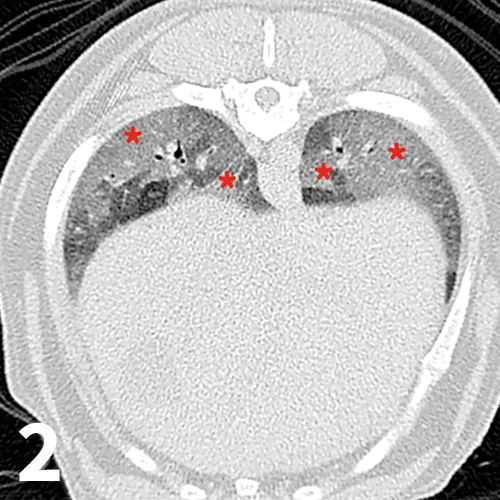

After 1 year of treatment, signs of CIPF and pulmonary hypertension were still under control. Lung crackles were still present on thoracic auscultation. A thoracic computerized tomography scan was performed under sedation to assess the distribution of lung parenchymal lesions (Figure 2). Lesions observed were compatible with those described in CIPF.1,2 Arterial blood gas analysis was performed under sedation and showed a pO2 of 51 mm Hg and a pCO2 of 41 mm Hg. The low arterial pO2 value is likely secondary to the severe underlying parenchymal lung disease and may have been compounded by the influence of sedation on the ventilation pattern (reduction in amplitude of respiratory movements).

Transverse thoracic precontrast CT images (lung window) of the same patient at the level of the caudal lung lobes. Scans revealed an almost generalized ground-glass opacity (red asterisks), visible as an increase in overall opacity of the lung parenchyma without obscuration of the underlying vessels in the accessory and caudal lung lobes.

Impaired arterial blood oxygen in a geriatric West Highland white terrier with progressive clinical signs and crackles audible on thoracic auscultation can lead to a clinicial suspicion of CIPF. However, definitive diagnosis of CIPF is challenging and relies on histopathologic examination of lung tissue,3 although thoracic high-resolution computed tomography (HRCT) may have a high specificity.1,2 HRCT findings include ground glass opacities, parenchymal bands, subpleural lines, subpleural interstitial thickening, peribronchovascular interstitial thickening, traction bronchiectasis, and honeycombing.1,2